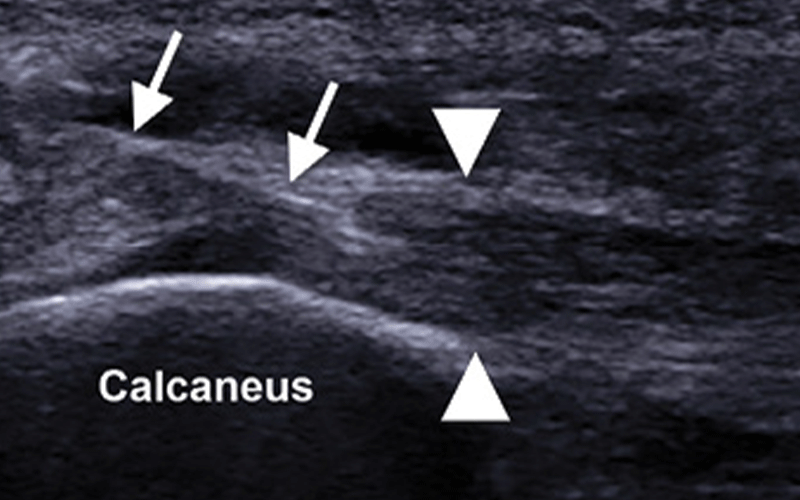

However, another study published that same year in the Journal of the American Medical Association found that PRP was no better than a saline injection in treating Achilles tendinosis.

Some of the strongest evidence favoring PRP came from a study Dr. Lee conducted on subjects with plantar fasciitis.

The study, “Acoustoelastography as an Outcome Measure for Platelet-Rich Plasma Injection Treatment of Chronic Plantar Fasciitis: A Pilot Study,” was funded by a 2010–2011 Toshiba America Medical Systems/RSNA Research Seed Grant.

In the study, half of the 44 subjects received PRP while the other half received steroids. Both groups experienced improvements in pain and function, but the PRP group continued to improve at the 32-week mark, just as the steroid group reported increased pain levels.